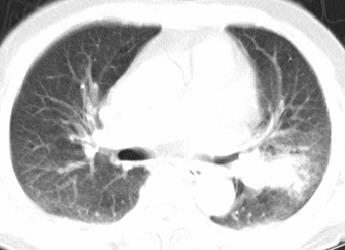

以下是引用xianxianzhongyi在2008-4-20 14:44:00的发言:[br]本人愚见:次病例短短两月的时间,呈现如此大面积实变,病变增长过于迅速,此其一。其二,病变在动脉早期既有明显强化。其三,左上叶后段及下叶背段多叶受累。其四,肺门及纵隔内未见明显肿大的淋巴结。估计层面较厚段支气管显示不清。 诊断:炎性实变可能性大。

以下是引用光影相伴在2008-4-20 14:39:00的发言:[br]支持:1)左侧中央型肺癌伴左肺上叶阻塞性肺炎。、[br] 2)双侧少量胸腔积液。